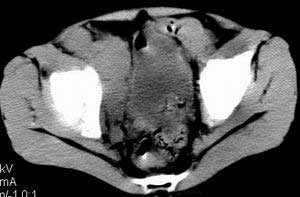

| 患者,男,9岁,因右下腹包块入院,血象不高,不规则发热,常超40度。 平扫: ![]() ![]() ![]() ![]() ![]() ![]() ![]() ![]() ![]() ![]() ![]() ![]() ![]() ![]() ![]() ![]() ![]() ![]() 增强: ![]() ![]() ![]() ![]() ![]() ![]() ![]() ![]() ![]() ![]() ![]() ![]() ![]() ![]() jiajie发言:骶椎右前区不规则软组织肿块,边缘光整,密度均匀,增强后均匀强化,右腹股沟区可见肿大淋巴结,临床有时发热,考虑淋巴瘤,儿童盆腔肿瘤应与神经母细胞瘤和横纹肌肉瘤鉴别。 longzhanghui发言:印象:盆腔右后壁不规则软组织肿块,并向前延伸.似为多个肿块融合,呈中等强化.初步考虑淋巴瘤. 听蝉观竹发言:右侧髂内、外组淋巴结肿大,从其形态和融合的情况看,同意大家意见-----考虑恶性病变,但是9岁男孩还要注意检查睾丸情况,有无隐睾? 常常类似情况是隐睾发生精原细胞瘤淋巴结转移,这个病例也要注意这一点!!! 广东凌发言:大家好,在这里我想说一下个人观点,我建议上传图片的同志能否辛苦一点就是把病史和图片都上传完整一点,比如这个病人的腹膜窗,并且这个病人的肠道的准备也是不怎么好,就从现有的质料看:病灶属于淋巴结肿大当无大的争议,有融合趋势,其内无坏死,边缘强化为主,故考虑:淋巴瘤!建议用腹膜窗看一下和肠道的关系! 阿圣发言:病灶属于淋巴结肿大当无大的争议,有融合趋势,其内无坏死,边缘强化为主,故考虑:淋巴瘤 结果是:淋巴瘤 病例来源:ct762。由宁静致远发布: http://www.radinet.com.cn/forum_view.asp?forum_id=4&view_id=2182 |